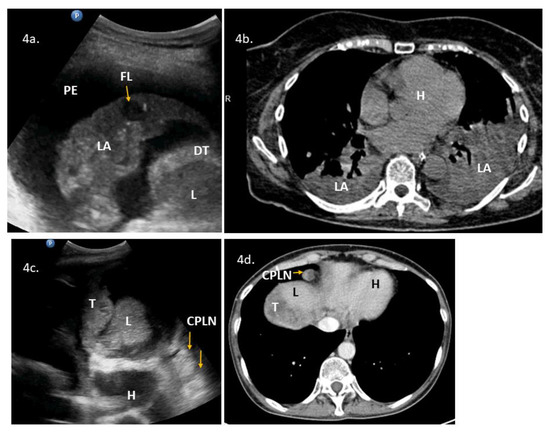

| 3 | 53 | 3 | ascites, massive pelvic involvement, omental involvement | abdominal diaphragm involvement **, pleural diaphragm involvement *, pleural effusions | - | Yes | Yes | YesScore: 6 → 8 Intermediate → High | No | 2c, 2d, 3a, VS2 | PDS, mucinous G3. R = microscopic |

| 4 | 48 | 3 | ascites, carcinomatosis, massive pelvic involvement, omental involvement | abdominal diaphragm involvement **, other *, pleural effusions | ascites, abdominal diaphragm involvement, carcinomatosis, massive pelvic involvement, other *, omental involvement, pleural effusions | Yes | Yes | YesScore: 7 → 9 Intermediate → High | No | 3b, 4c, 4d, VS3 | PDS attempt because of low bowel obstruction symptoms. HGSOC, R > 1 cm. * suspected enlarged cardiophrenic lymph nodes |

| 5 | 79 | 3 | ascites, carcinomatosis, omental involvement | abdominal diaphragm involvement **, pleural effusions, spleen involvement | - | Yes | Yes | Yes Score: 4 → 8 Intermediate → High | No | 3c, 3d, VS4 | DLSK, HGSOC, NACT |